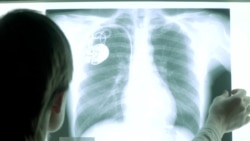

Ира, московский курьер, ходит зимой и летом в ветровке, бьется током, постоянно двигается и спит по 4 часа в день. Она уже 16 лет живет с электрокардиостимулятором.